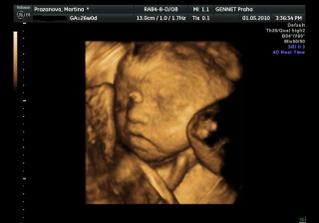

Určitě dám sem vědět i s aktuální fotečkou. Jména mám v pase. A 1.května jdeme na 4D UTZ, tak se moc těšíme 🙂

Letí to jak blázen, vždyť to znáš 🙂. Zatím nevíme nic, ale zítra jdeme na velký genetický UTZ, tak snad tam prcek nebude sedět v tureckém sedě jako minule 🙂))